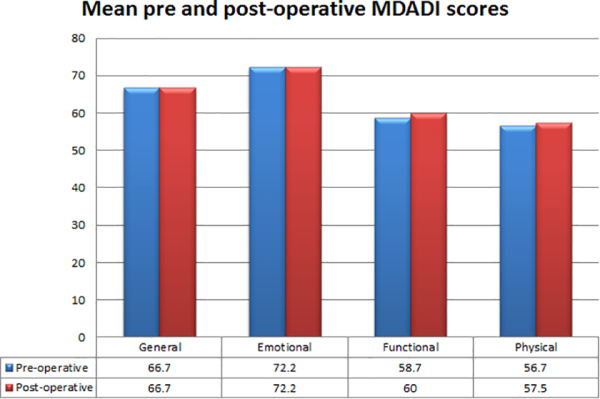

Comparison of UWQOL scores did not show any considerable difference in QOL between the pre-and postoperative period; however, small improvements were noted in activity, chewing and anxiety scores, and no change or mild reduction seen in the remaining domains (Figure 3). Similarly, mean MDADI scores did not show any substantial difference across all domains, with global and emotional scores being identical pre- and postoperatively (G 66.7 vs 66.7, E72.2 vs 72.2) and functional and physical (F 58.7 vs 60, P 56.7 vs 57.54) scores demonstrating a slight improvement posttreatment (Figure 4).

Figure 4

Graph and table summarizing mean preoperative (blue) and postoperative (red) MD Anderson dysphagia inventory scores.